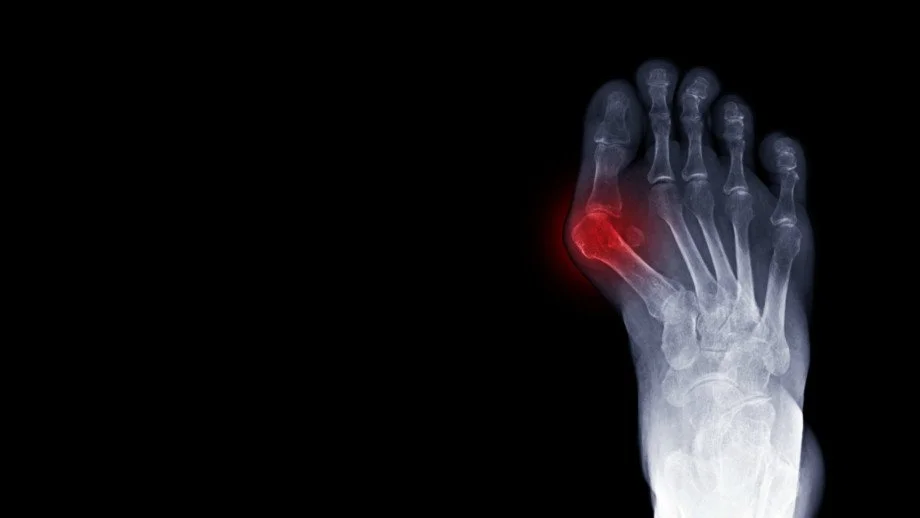

We strive to restore your foot & ankle function using the the least invasive treatment possible so you can get back to on your feet. Dr. Henry uses both nonoperative treatments and surgeries to get you back to doing what you love. These are just some of the procedures Dr. Henry specializes in.

Through a joint decision-making process, we may recommend surgical treatment if we believe the potential benefits outweigh the risks. For patients with chronic (long-term) conditions, the decision for surgery may come after a period of nonoperative treatment, including shoewear changes, orthotics (shoe inserts), ankle/foot braces, physical therapy, medication, activity optimization, and injections. You will discuss this in your consultation with Dr. Henry.